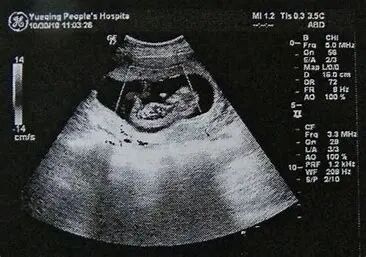

超声,也称为超声波成像,超声波成像的物理原理基于超声波在人体软组织中的反射、折射和衰减现象。当超声波发射到人体内部时,它们会遇到不同密度和弹性的组织界面。由于这些界面的声阻抗差异,部分超声波会被反射回来,而另一部分则会穿透这些界面继续传播。反射回来的超声波被探头接收,并转换为电信号。这些电信号经过放大和处理后,被转换成可视化的图像。

超声是一种无创、无痛的医学成像技术,广泛应用于妇产科、心脏病学和腹部器官的检查。